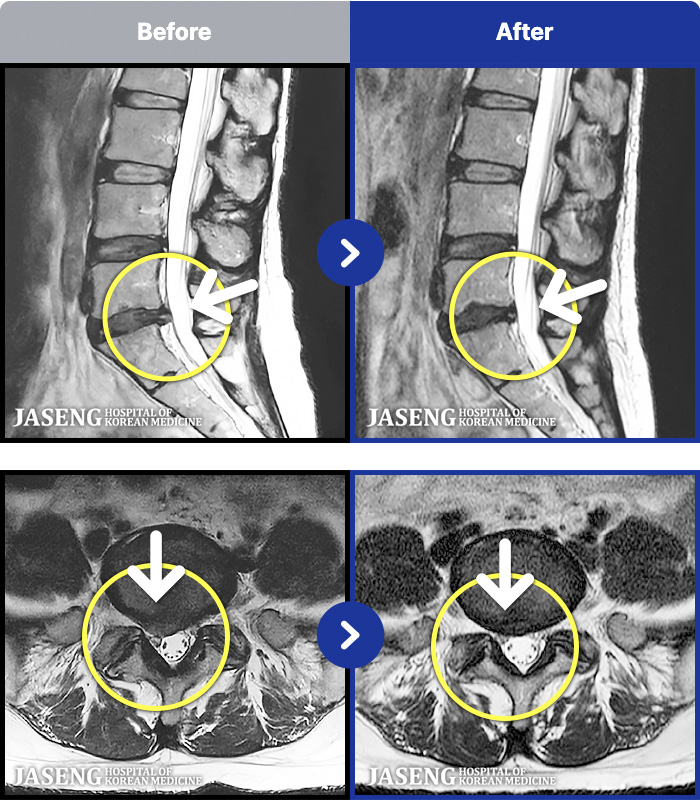

1,287 MRI ũ ʸ Ȯϼ.